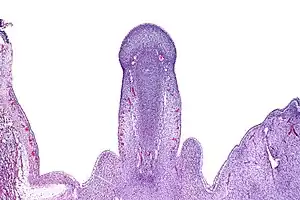

In embryology, the primordial phallus refers to the clitoris of a female or the penis in the male, particularly during embryonic development of the urinary and reproductive organs, before sexual differentiation is evident. This is also the case for the immature male analog, the immature glans penis.